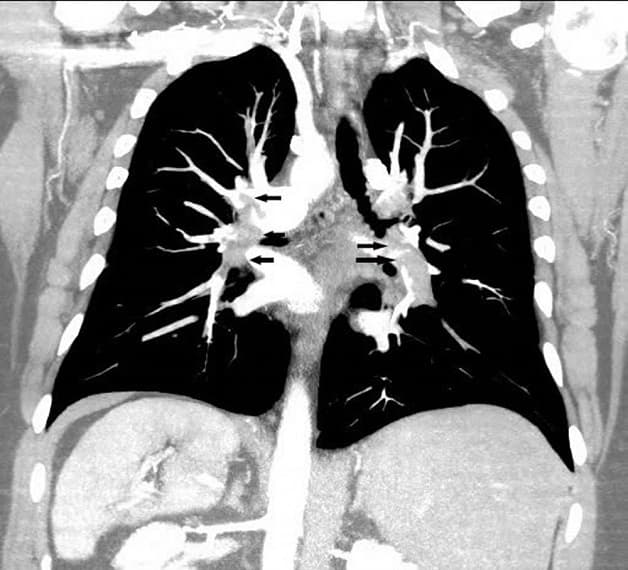

Chụp cắt lớp vi tính (chụp CT) hệ tiết niệu sử dụng tia X để tạo ra các hình ảnh chi tiết về một bộ phận cơ thể đang được kiểm tra. Những hình ảnh này sau đó được gửi đến máy tính và nhanh chóng được dựng lại thành hình ảnh 2D rất chi tiết.

Phương pháp sử dụng thuốc nhuộm tia X (dung dịch cản quang i-ốt) được tiêm vào tĩnh mạch ở bàn tay hoặc cánh tay người bệnh. Thuốc nhuộm chảy vào các cơ quan tiết niệu như thận, niệu quản, bàng quang và phác thảo hình ảnh những cấu trúc này. Hình ảnh X-Quang được thực hiện vào những thời điểm cụ thể trong quá trình. Từ đó bác sĩ có thể nhìn thấy rõ đường tiết niệu bệnh nhân, đánh giá hoạt động hoặc tìm kiếm bất thường ở bộ phận này.

Các bác sĩ sử dụng CT Scanner niệu đồ để kiểm tra hoạt động của hệ thống tiết niệu, bao gồm thận, bàng quang và niệu quản trong cơ thể. Các bác sĩ có thể sử dụng hình ảnh sau chụp bằng kỹ thuật để xem liệu các cấu trúc bên trong hệ tiết niệu có khỏe mạnh và hoạt động chính xác hay không cũng như để kiểm tra bất kỳ dấu hiệu bệnh nào.